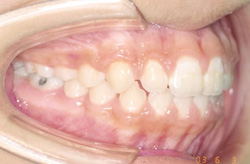

16歳0ヶ月の写真です。美しい歯並びになっており、咬みあわせも良い状態になりました。前歯が3本しかありませんでしたが、3本抜歯をすることで、左右対称な歯並びになりました。

- 治療方法

- 下顎右側側切歯の先天欠如を伴う過蓋咬合症と診断し、マルチブラケット装置にて上顎両側第一小臼歯、下顎左側第一小臼歯を抜去して治療